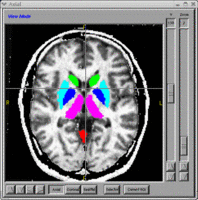

- BRAINSCut - Automated segmentation of subcortical and cerebellar regions of interest using an artificial neural network. NITRC Link